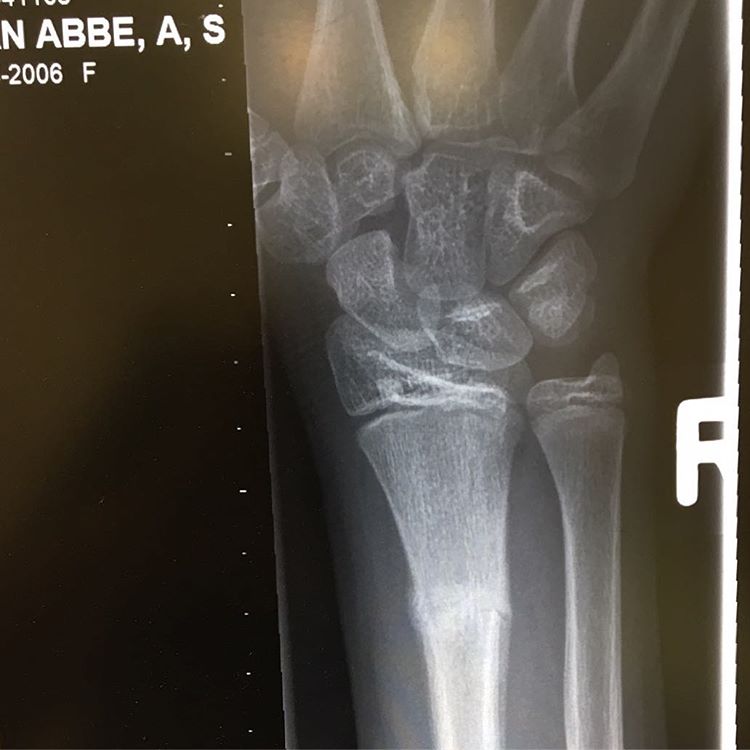

Oh noes!!! Lie has been walking around with a broken arm for the last THREE weeks... greatful that it will heal nicely #badparenting #fighter #stronggirls